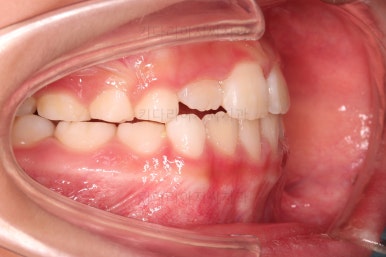

치료 4개월째인데요.

열심히 모범적으로 잘 사용해 주었고, 앞니가 아슬아슬하게 앞니끼리 맞물리는 상태까지 개선이 되었네요.

치료 6개월째입니다.

반대교합은 잘 개선되었는데요.

혀/입술 근육 훈련을 위해서 더 사용하기로 했으며 마침 윗니 작은 앞니도 맹출하는 중이라 해당 치아의 맹출 경로를 안내해 주는 역할로 프리올소를 더 사용하기로 했습니다.